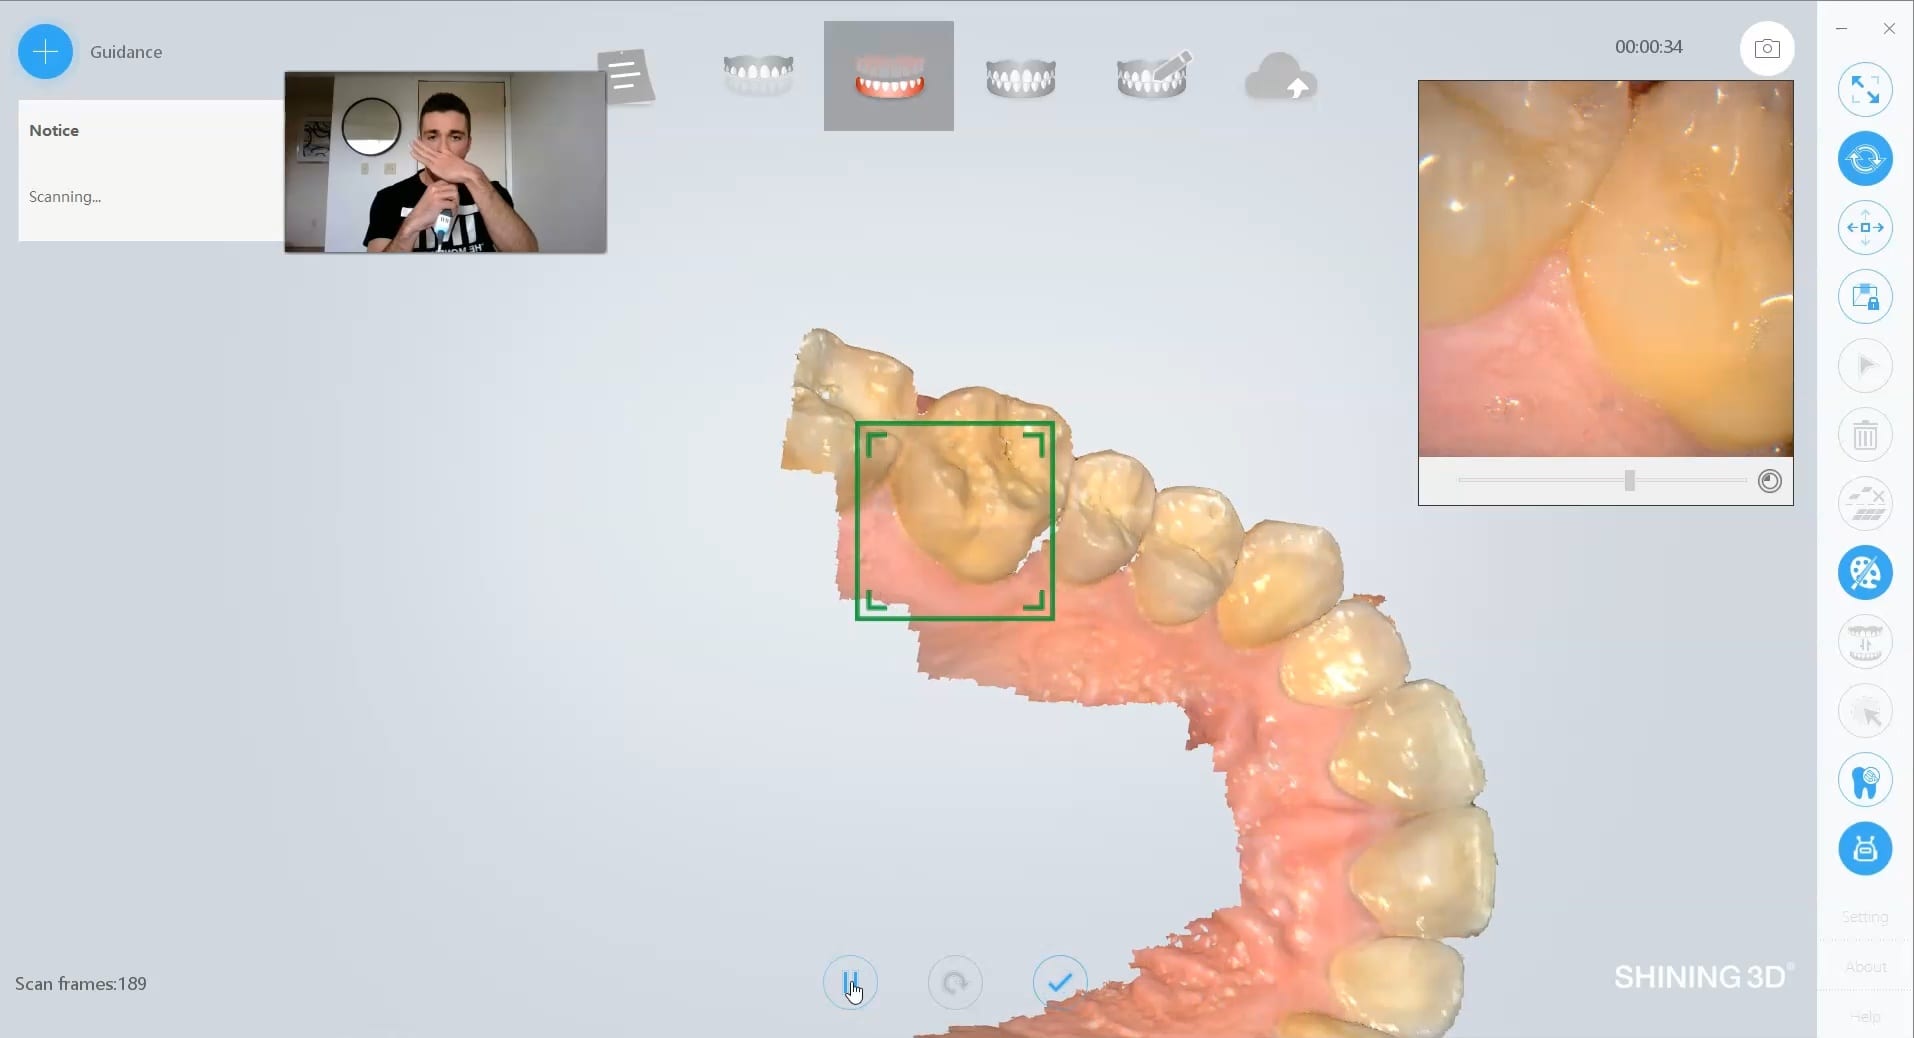

Full Arch Scan by The Shining 3D Aoralscan

March 16, 2020In this video we demonstrate how the Aoralscan can complete a full arch scan utilizing the basic principles of digital impressioning. Proper retraction, isolation, and scanning technique lead to high […]